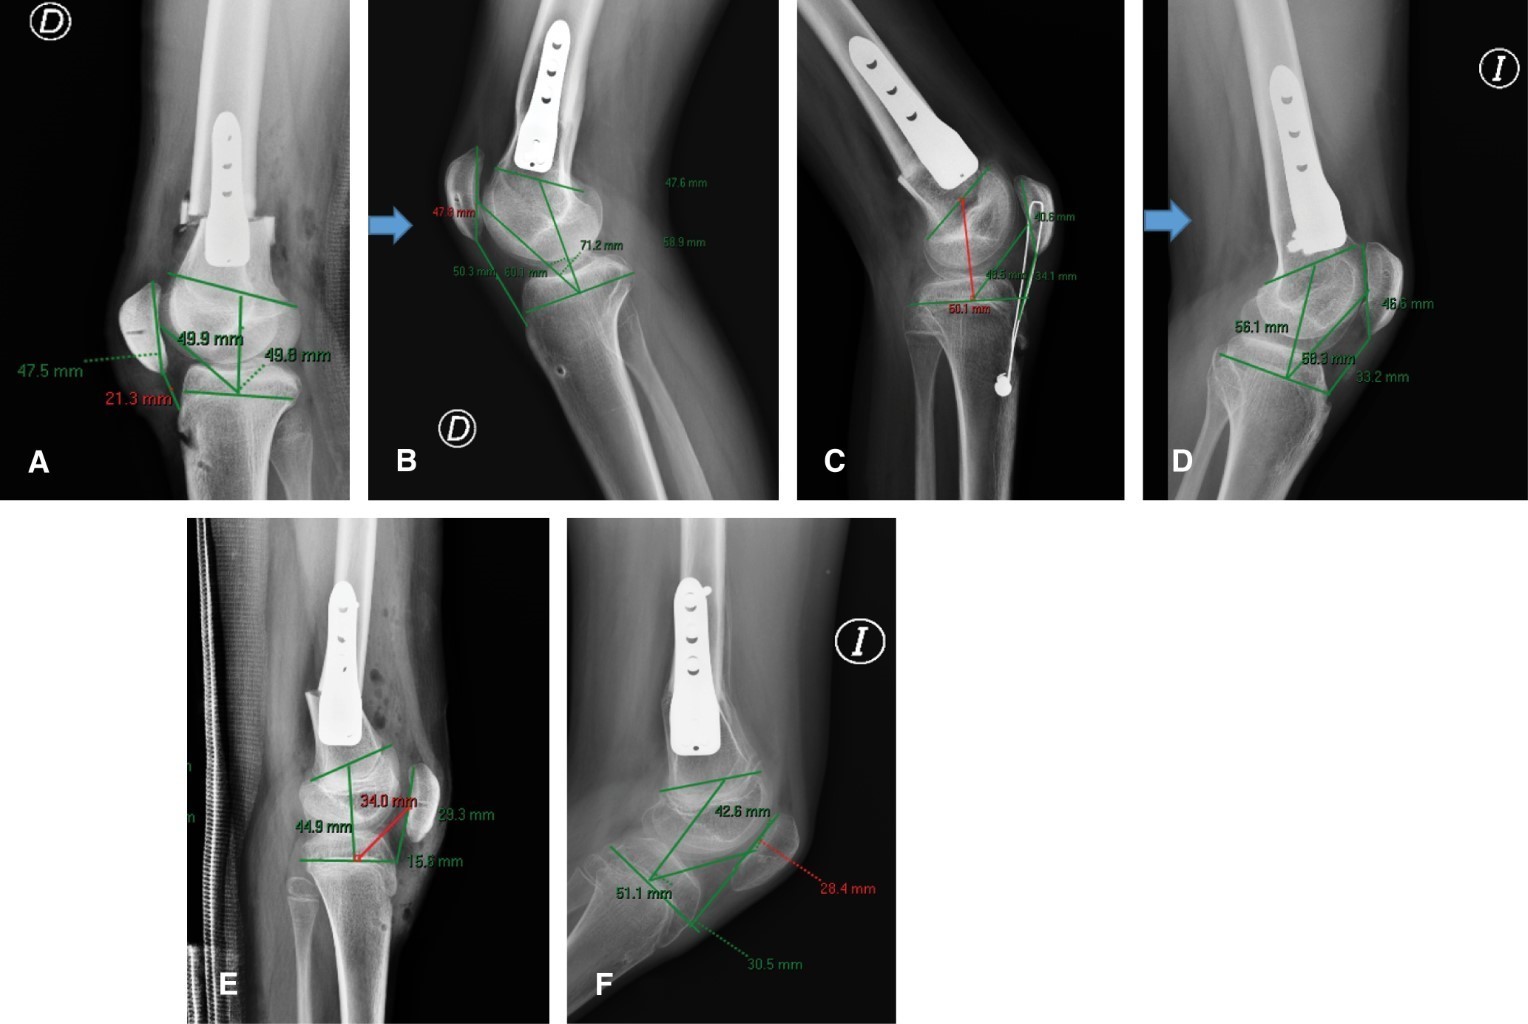

A continuación, en la Figura 3 se muestran ejemplos radiográficos del postquirúrgico inmediato y a los 24 meses de seguimiento con los tres materiales utilizados.